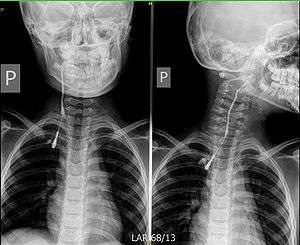

Fistulography of a right branchial cleft sinus. | |